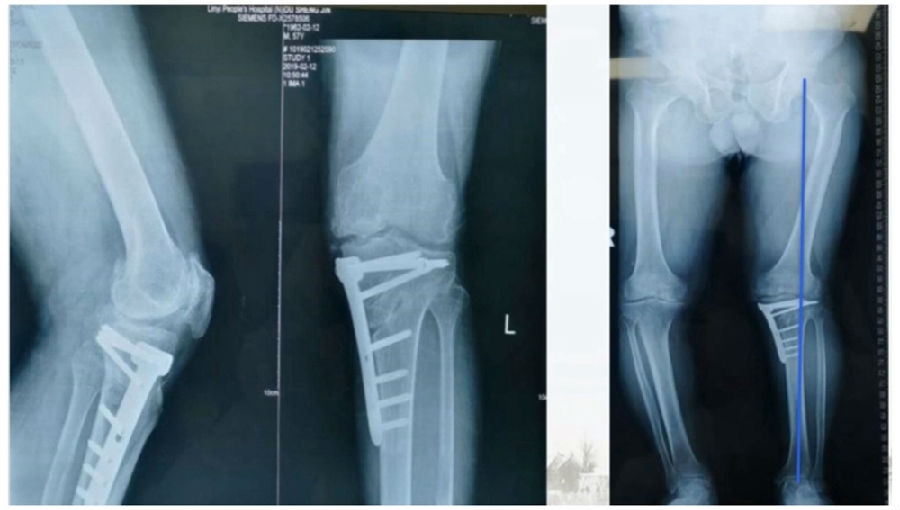

典型病例,男性,65岁,农民,双膝内翻16度。

术前影像

第一次为该患者做了传统上行开放截骨,撑开角度较大,术后用三种方法测量髌骨高度,发现髌骨高度受到影响,髌骨变低了。

左膝上行OWHTO(初次)

上行OWHTO髌骨高度测量

ISI法测量髌骨无明显变化;CDI、BPI法测量髌骨降低明显;患者屈膝锻炼困难。

第二次来院做另一侧肢体时,采用下行截骨,术后患者髌骨高度,无论用哪种方法测量都无明显变化,而且患者膝关节功能迅速得到恢复。

右膝下行OWHTO(再次)

下行OWHTO髌骨高度测量

ISI法测量髌骨无明显变化;CDI、BPI法测量髌骨无明显变化;患者屈膝明显改善。